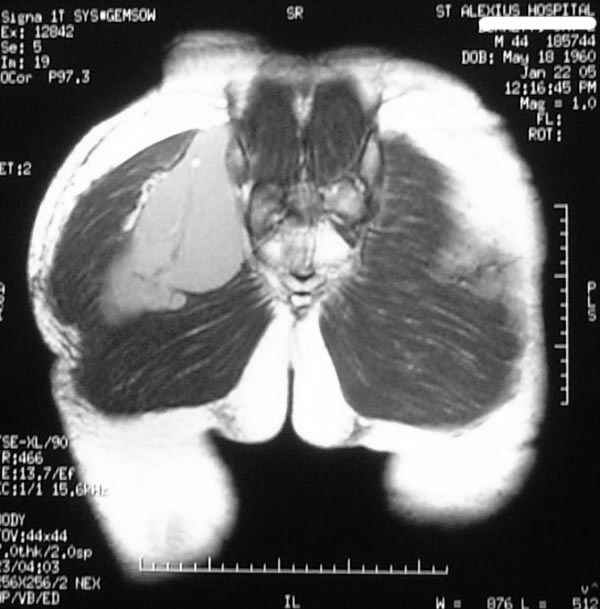

Уважаемые коллеги,Неоднократные пункционные эвакуация (3 раза) крови изягодичной области, после полученной пройзводственнойтравмы (более 1.5 мес) ударом в ягодицу тяжелым, около полутонны предметом.

Рентгенограмма без особенностей, несмещенные переломы лонной и седалищных костей таза.Последная пункция 10 дней назад 180 мл темной крови, после пункции сделано магнито-резонансные исследование (на снимках), какой диагноз и тактика дальнейшего лечения, какие рекомендации?Джолдас Кульджанов

Djoldas Kuldjanov, M.D. 06 Март 2005, 00:25

Разбираемый случай немного отличался от классического Degloving Injury

или Morel-Lavalle Lesion, которые часты при переломах ацетабулума и

костей таза. Состояние, наблюдаемое после удара, в результате чего

образуются обширные полости в тазобедренной области: ягодицы или

большого вертела. Как описал Анатолий, обширные полости заполняются

кровью, затем синовиальной жидкостью, отодвигают сроки операции или

после операции приводят к осложнениям послеоперационных ран.

Лечение повреждений Morel-Lavalle проводится в условиях операционной,

через 3-4 дня после травмы, из маленького (2-3 см) разреза производят

эвакуацию густой пастообразной гематомы, полость промывается и

очищается щеткой изнутри, затем закрывают рану с дренажом, обычно

через 4-5 дней полость затягивается.

Описанный случай:

В промежутке около месяца 3 пункции с удалением около 180 мл крови

каждый раз. После исследовании МРТ было принято решение - удаление

гематомы в операционной более широким доступом. Во время операции -

под ягодичной мышцей была капсула, где скопилось около 700 мл

гематомы, после удаления в полости обнаружили несколько закупорившихся

вен и краевой разрыв одной из двух ветвей нижней ягодичной артерии.

После промывания, гемостаза и дренажа, по рекомендации хирурга стенку

полости обработали спреем Tisseel, специальным склерозирующим

препаратом, применяемым пластическими хирургами, затем зашили рану.

Дренажи удалены на 5 день, рана зажила первично. Случай был интересен

применением препарата Tisseel Fibrin Sealant для склерозирования

полостей, только недавно получившим разрешение к применению, хотя по

аннотации в Европе и в Южной Америке применяют давно.